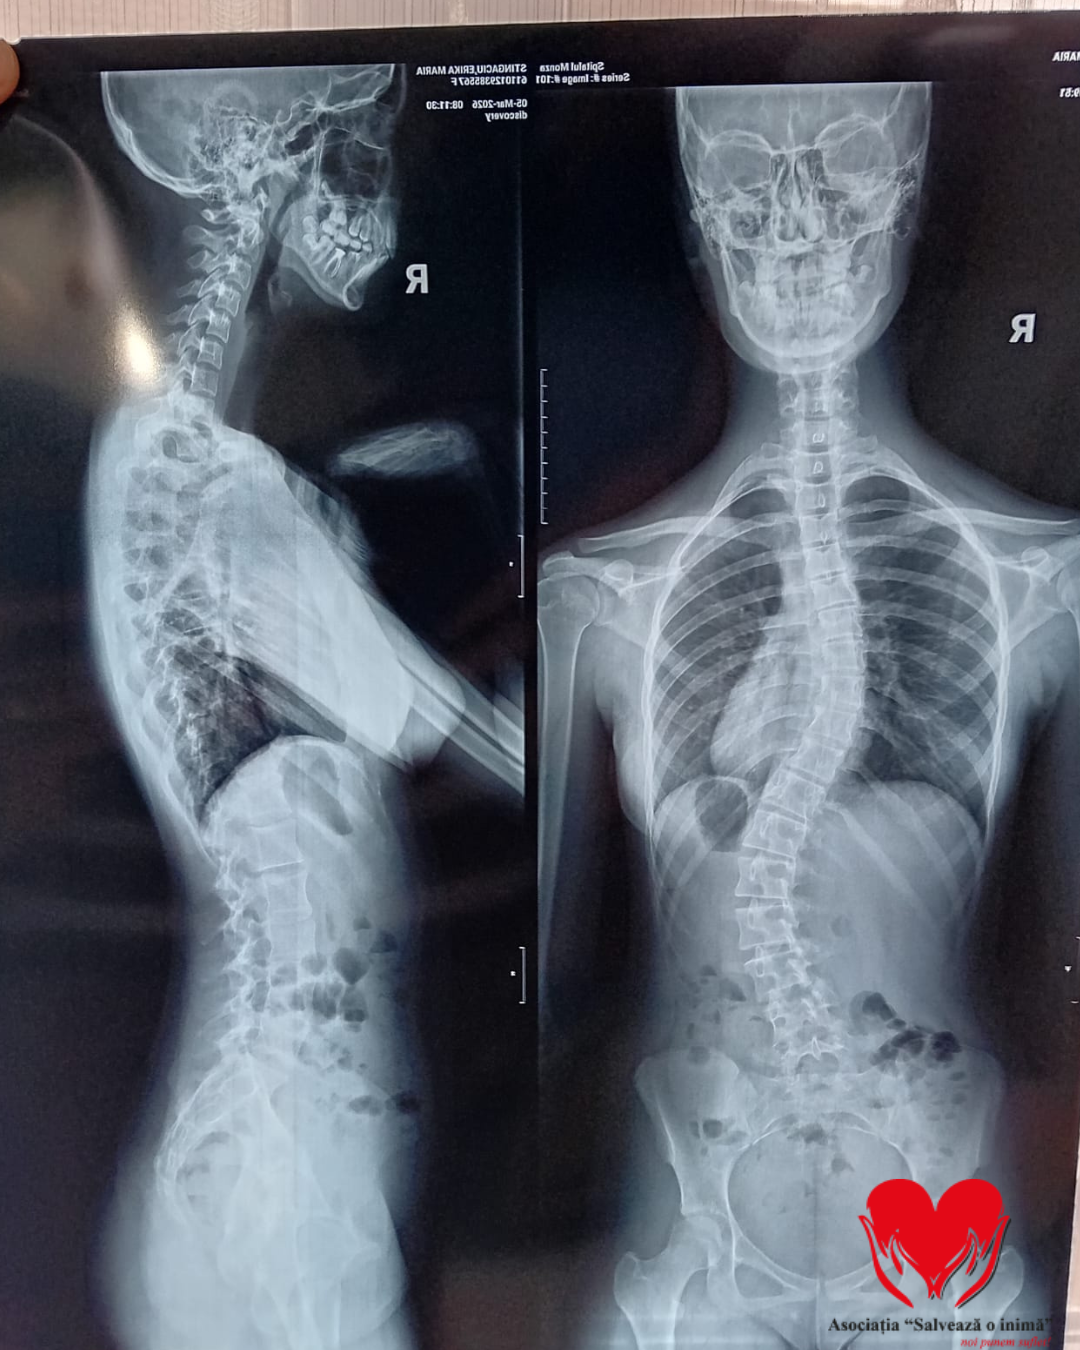

Erikai Maria Stingaciu este o adolescentă de 15 ani care se confruntă cu un diagnostic sever de scolioză dorsolombară progresivă, o afecțiune care îi modifică zilnic postura și îi afectează profund calitatea vieții.

Până în urmă cu doi ani, Erika era un copil obișnuit, cu planuri simple și o copilărie trăită firesc. Totul s-a schimbat în februarie 2024, când, în urma unui consult aparent banal, medicul a observat o asimetrie la nivelul umerilor. Investigațiile ulterioare au condus la stabilirea diagnosticului de scolioză idiopatică lombară, iar de atunci viața ei a devenit o luptă continuă pentru a încetini evoluția afecțiunii.

A urmat zilnic ședințe de kinetoterapie, a purtat un corset rigid tip Cheneau timp de 23 de ore din 24 și a trecut prin multiple consultații și investigații în centre medicale din țară. În ciuda tuturor eforturilor, evoluția a continuat, iar în februarie 2026, în urma unui nou control, medicii au confirmat caracterul progresiv al scoliozei și necesitatea unei intervenții chirurgicale.

În prezent, Erika continuă să poarte corsetul zilnic și să urmeze terapii, însă acestea nu mai pot opri evoluția deformării coloanei. Singura soluție rămasă este intervenția chirurgicală, care îi poate reda șansa la o viață fără durere și fără limitările actuale.